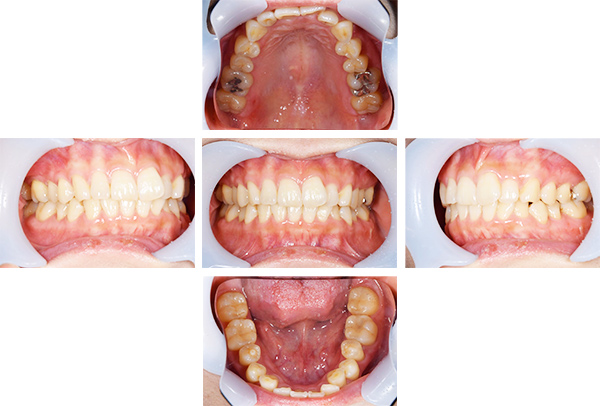

症例写真(治療前)

担当医師所見

治療前:

八重歯が目立ちます。また銀歯もおおく、見た目が気になります。虫歯も散見できます。

レントゲン写真(治療前)

根の治療を3本すでに治療されています。1本根の奥の詰め物が疎になっていますので、根の部分の再治療も行う必要がありそうです。銀歯の中で虫歯になっているものもあります。

治療中

矯正装置をつけています。だんだん八重歯が動いてきているのがわかります。今回のケースでは、抜歯を行わずに矯正ができました。

症例写真(治療後)

治療後:

矯正治療と虫歯の治療すべて終わったときの写真になります。見た目も最初の頃とは全く違いますし、お口の中もすごく綺麗です。

治療

方針

まずは虫歯の治療を行い、被せ物をする部分は仮歯をいれて矯正を行う。矯正終了後、仮歯の部分を最終的な被せ物に変えていく。また気になっていた銀歯もセラミックに変えて終了となった。

内容

セラミックインレー、オールセラミックプレミアム、矯正

特記

事項

虫歯の治療によって歯が一時的に染みるようになる可能性があります。また、歯を抜かずに矯正を行っていますが、全ての方で歯を抜かずに矯正ができるわけではありません。